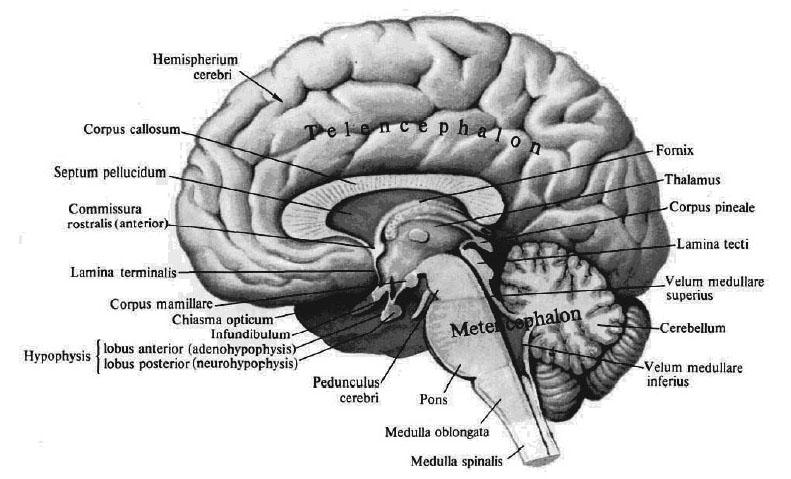

Анатомические снимки верхнелатеральной поверхности головного мозга